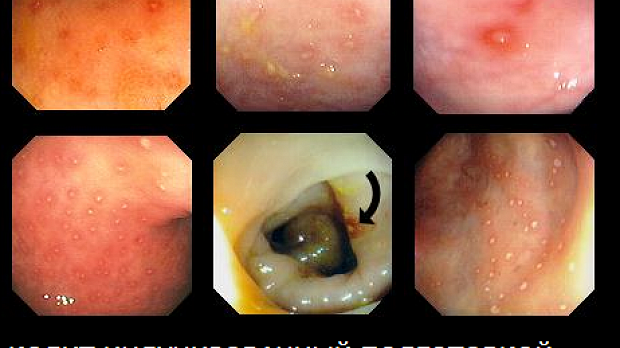

Индуцированные подготовкой колиты одна из актуальных проблем отечественной гастроэнтерологии.

Индуцированные подготовкой колиты одна из актуальных проблем отечественной гастроэнтерологии. До появления современных препаратов на основе ПЭГ использовались сомнительные препараты на солевой основе приводившие к тяжелым осложнениям.